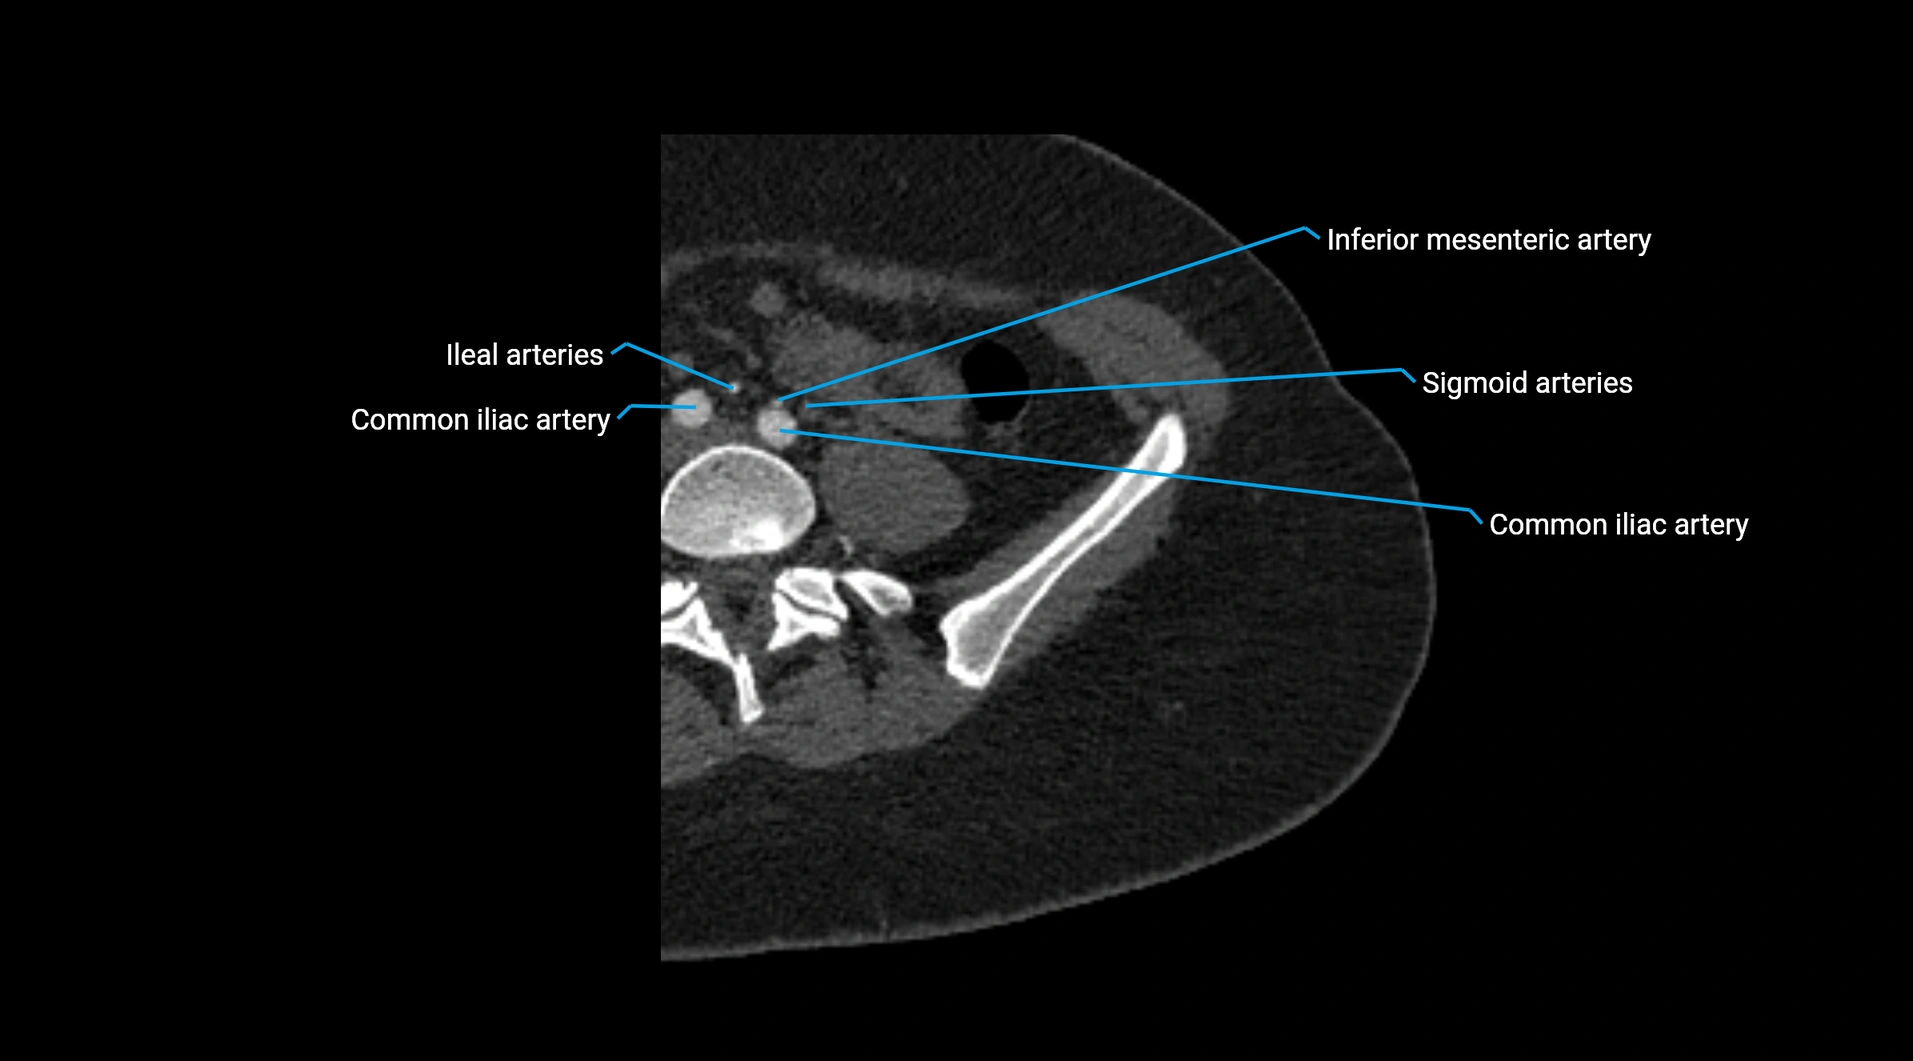

• Unpaired visceral branches: celiac trunk, superior mesenteric artery (SMA), inferior mesenteric artery (IMA)

• Terminal branches: right and left common iliac arteries

Contrast-enhanced CT (CTA):

• Gold standard for abdominal aortic imaging

• Provides excellent detail of lumen, wall, aneurysm, thrombus, and branch vessels

• Multiplanar and 3D reconstructions help in aneurysm measurement, stent graft planning, and dissection evaluation